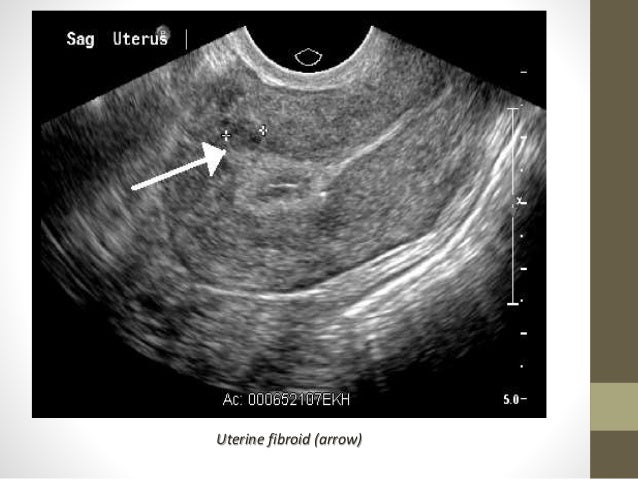

Фибромиома матки что это такое узи - фото презентация